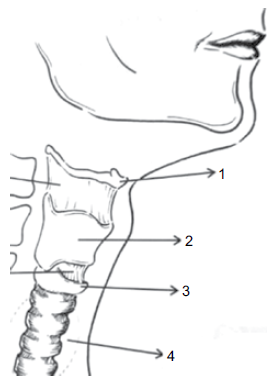

Observe a figura a seguir.

(Mara Behlau. VOZ: O livro do Especialista (volume 1). Rio de Janeiro: Editora Revinter. p. 04)

Assinale a alternativa que denomina, correta e respectivamente, as estruturas numeradas.